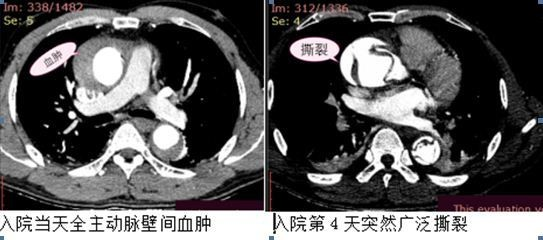

三位患者均以突发急性胸痛入急救中心,在急救中心做主动脉CTA检查明确诊断,其中2例女性患者同时合并全主动脉壁间血肿及多发穿透性溃疡,1例男性患者诊断全主动脉壁间血肿。

三例病人均在常规严密监护下精心治疗,适时选择手术时机。两例患者比较平稳,三周后,虽然血肿明显缩小,但是有的溃疡灶变大、有的形成小夹层,也应该手术,所以三周后顺利成功行介入覆膜支架植入手术。另一例男性患者,入院后病情趋于稳定,第4天时感到明显好转,但在正常排便时,突然病情加重,急查CTA血肿变逆撕为A型夹层,明确病情更加凶险,趋于破裂,急转胸外科,开胸手术,所幸抢救成功,保住了性命。可见壁内血肿,穿透性溃疡,同主动脉夹层一样,同样具有高风险。

本次就诊的三例患者通过手术治疗挽救了生命,男性患者入院第4天轻微诱因(排大便)即出现胸痛加重,病情迅速加重,刘清泉主任指出,壁内血肿和主动脉穿透性溃疡的临床特征与急性主动脉夹层相似,其中一种病理状态可进展至另外一种,这三者之间存在重叠征象,而且主动脉壁内血肿及主动脉穿透性溃疡同样具有高风险、高死亡率。这样人体的不定时炸弹也需要及早清除。